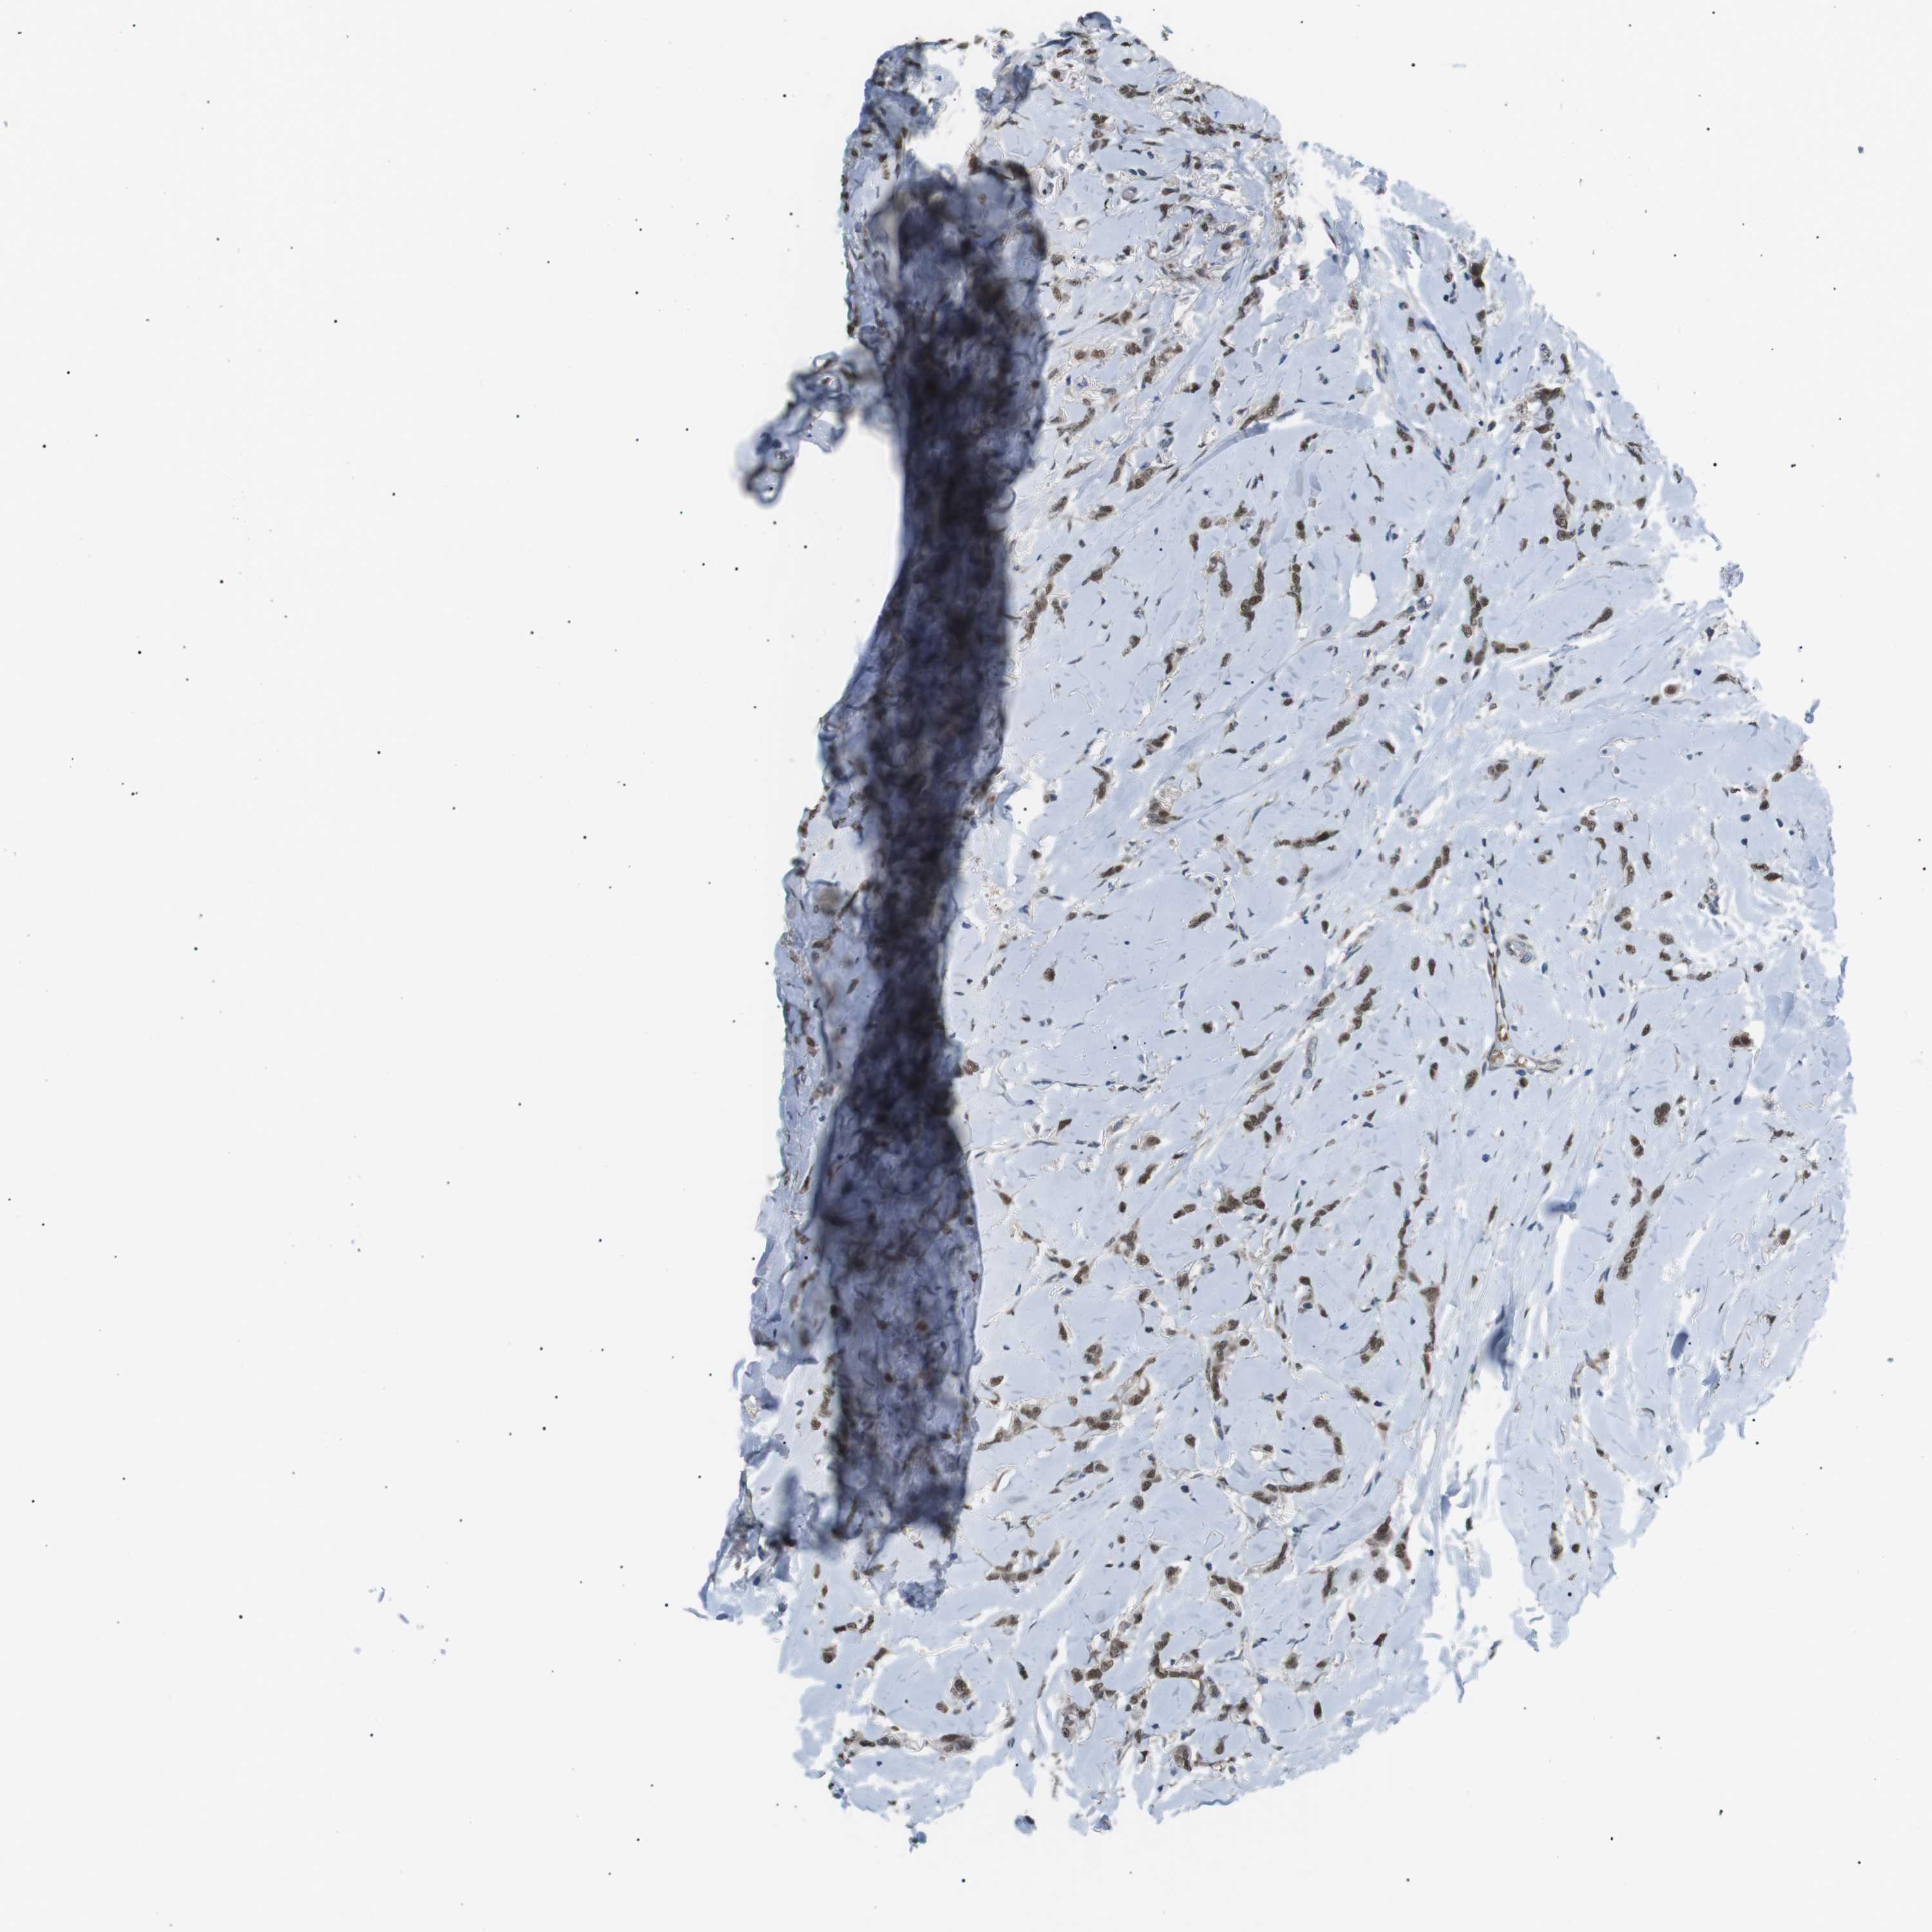

BRCA TCGA BRCA VALIDATION PROTEIN EXPRESSION